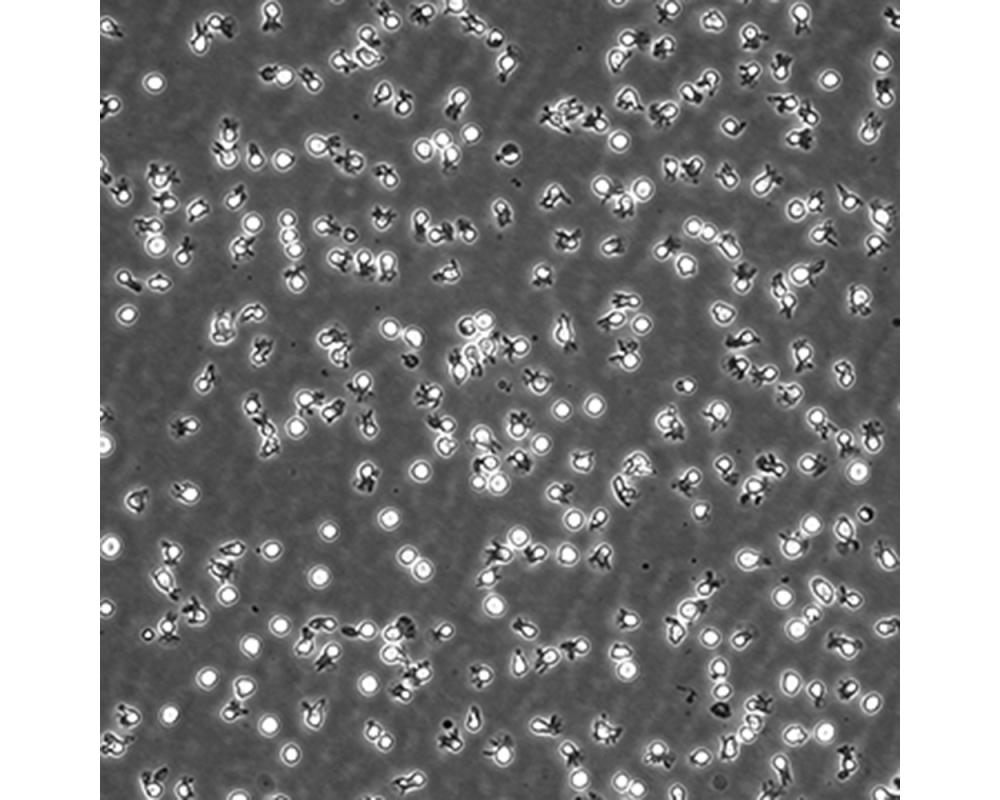

中文名稱 人彌漫大B細胞淋巴瘤細胞

組織來源 彌漫大B細胞淋巴瘤;男性

生長特性 懸浮

培養基 IMDM,90%;FBS,10%;雙抗。

培養條件 Atmosphere: Air, 95%; CO2, 5%。Temperature: 37℃